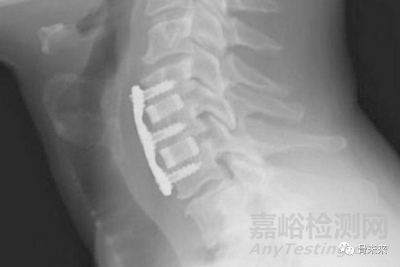

無(wú)論何種成像方式,氮化硅植入物都能提供良好的成像。

成像質(zhì)量具備多個(gè)優(yōu)勢(shì),可以提供植入物的精確視圖,能夠讓醫(yī)生精確進(jìn)行術(shù)中植入物放置和術(shù)后融合評(píng)估。

2. 成像質(zhì)量?jī)?yōu)越

氮化硅植入物具有半輻射特性,邊界清晰可見(jiàn),在 MRI 下不會(huì)產(chǎn)生變形,在 CT 下也不會(huì)產(chǎn)生散射。